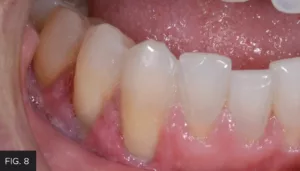

Excess composite was removed, and the restoration was shaped using a thin tapered diamond bur. Coarse and medium grit Contours™ Finishing and Polishing Discs (Clinician’s Choice) were used to smooth and refine the restoration. Finally, the A.S.A.P.® 2-step diamond polishing system (Clinician’s Choice) quickly created a high-luster polish, essential for preventing stain and plaque formation and contributing to the longevity of the restoration.

The one-week follow up photo shows how well the tissue healed after utilizing the Bluewave laser. (FIG. 8)